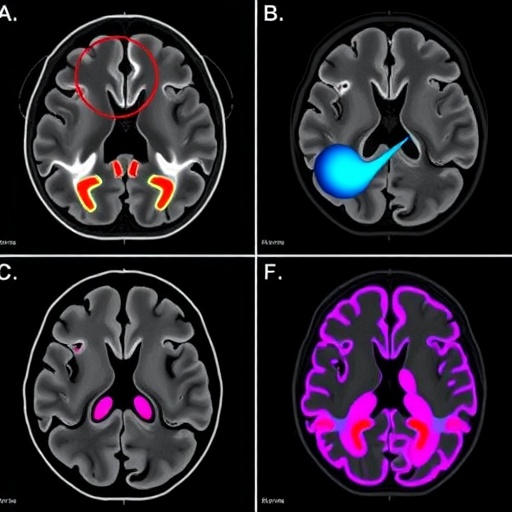

The team’s use of super-resolution ultrasound imaging represents a technical leap forward, delivering nanoscale insight into the microvascular architecture and perfusion without the invasiveness or optical limitations inherent to other modalities like two-photon microscopy or functional MRI. By harnessing ultrafast plane wave imaging combined with advanced signal processing algorithms, the researchers achieved unprecedented spatial resolution and temporal sensitivity to map cerebral microvasculature and blood flow patterns intimately coupled with neuronal populations in the substantia nigra.

Importantly, the imaging approach relied on indirect markers of neurovascular coupling by simultaneously measuring microvascular blood volume changes and correlating these with neuronal functional states. This nuanced methodology allowed the team to parse out discrepancies between neuronal firing and the expected hemodynamic response, effectively revealing regions where the vascular system fails to adapt adequately to neural demands. These areas of impaired neurovascular coupling were conspicuously concentrated within the substantia nigra of Parkinson’s disease model animals, thereby implicating vasculature dysfunction as a co-conspirator in dopaminergic neuron vulnerability.

The researchers meticulously validated their imaging results against established histological and biochemical markers of neuronal health and vascular integrity, confirming the robustness of the technique. By establishing these correlations, they ensured that the subtle vascular abnormalities detected were truly reflective of disease-relevant pathology. Notably, the identification of neurovascular uncoupling in the substantia nigra aligns with recent hypotheses that microvascular dysregulation may contribute to the selective vulnerability of dopaminergic neurons observed in Parkinson’s disease.